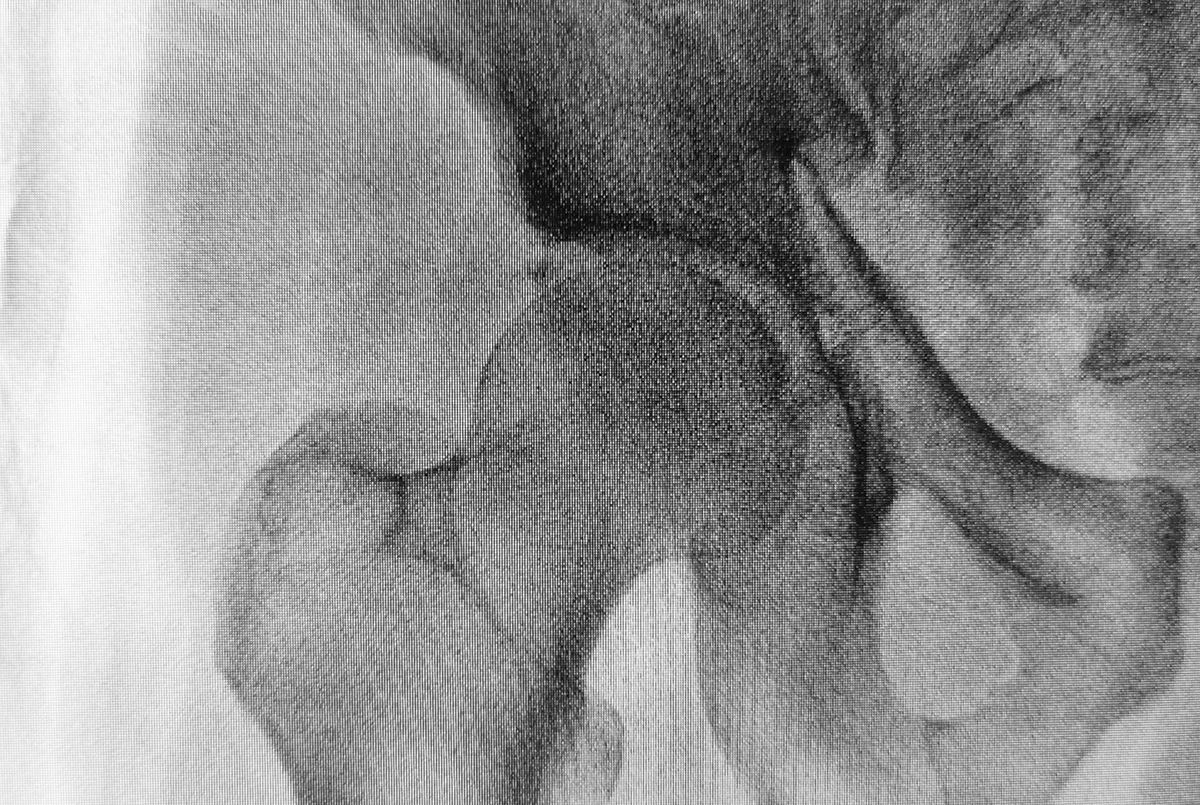

在療癒過程中,Jasmin老師找出她腰部、腿部多年的疼痛原因,在她20歲的時候發生了一場嚴重車禍,

當時是由她的表姊騎乘,坐後座的她因為撞擊猛烈因此受重傷,住院長達半年之久,可是表姊只受到輕傷